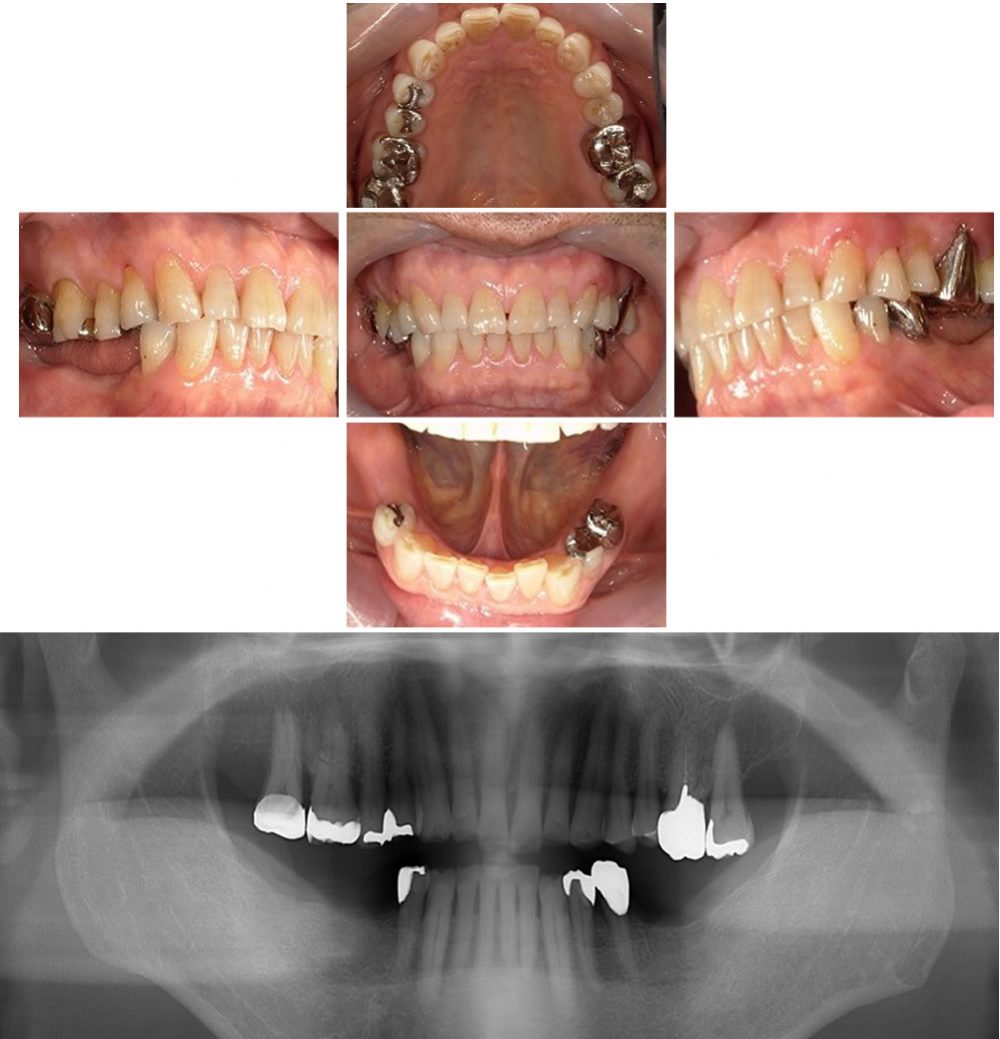

見えにくいクラスプと金属床の部分義歯で治療した症例

下の入れ歯が痛くて入れてない、痛くて噛めないことを主訴としご来院された患者様に目立たないクラスプ(金属のバネ)と金属床の部分義歯を用いて咬み合わせを回復した症例をご紹介します。

初診時の口腔内

患者様は60代の男性です。現在、入れ歯は痛くて入れていないということでした。お口の中の状態を調べるためにパノラマX線撮影をしました。初診時の口腔内写真とパノラマX線写真です。

左右側ともに上の奥歯が下に伸びてきてしまっています。また、咬み合わせが強く下の前歯の切端が大きく削れています。

下の奥歯に義歯を入れるスペースを確保し、さらに金属床にしたことにより以前より薄く異物感が軽減したとのことで患者様の満足を得られました。

| 年齢・性別 | 60代男性 |

| 治療期間 | 6ヶ月 |

| 治療費 | 約660,000円/税込(上顎:かぶせ物治療/下顎:義歯治療) |

| リスク・注意点 | 義歯は取外し可能なものですので、日常的なお手入れが必要です。 |